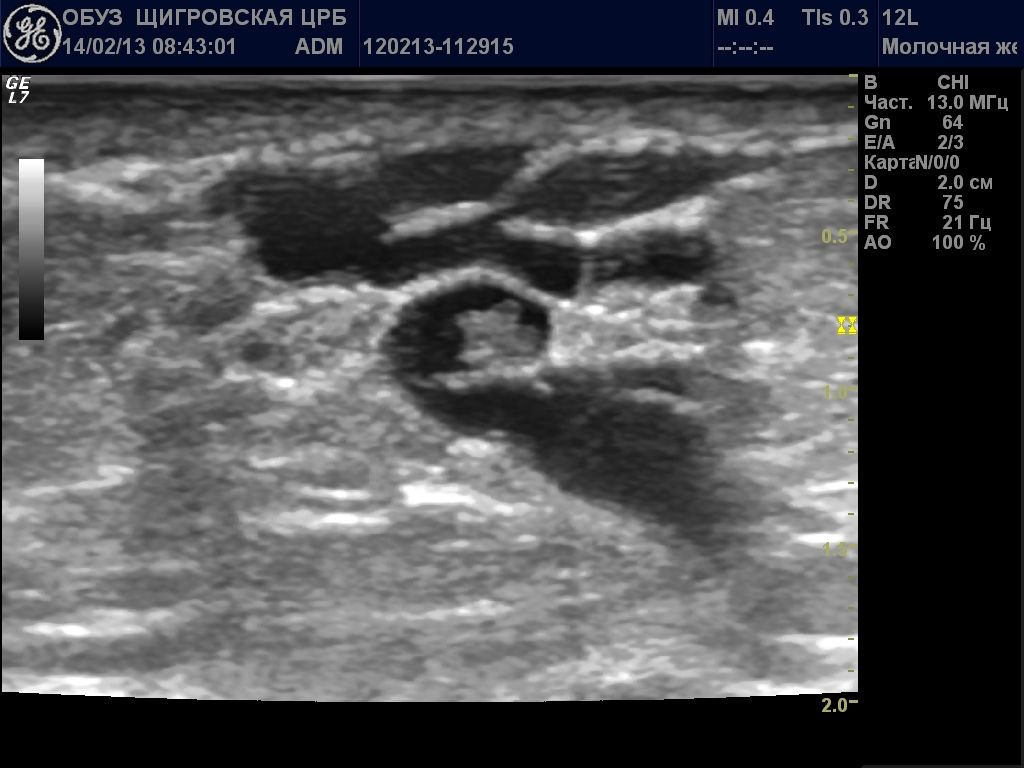

Непременно выполняется ультразвуковое исследование молочной железы. Данный метод достаточно информативен и безопасен. УЗИ помогает выявить размеры новообразования и его структуру. На руки пациенту выдается фото сканирования железы.

Обследование также включает тонкоигольную аспирационную биопсию. Метод помогает отличить кистоз от фиброаденомы. Эти два заболевания имеют одинаковую симптоматику. С помощью пункции определяются цвет и характер жидкости в кисте, а также образование гнойных инфильтратов. В особенных случаях проводится цистологическое исследование биоматериала, которое опровергает или подтверждает онкологию.

- Ультразвуковое исследование.

- Тонкоигольная аспирационная биопсия кистозного образования – один из наиболее информативных методов диагностики заболевания, так как симптоматика кистоза достаточно созвучна с проявлениями фиброаденомы. Диагностика обоих этих заболеваний несколько проблематична. В свете различных методик лечения, установить правильную причину патологии просто необходимо. Данную пункцию медики относят как к диагностическим методам исследования, так и к лечебным процедурам молочной железы. Ведь констатировать кисту уже можно на стадии пунктирования, оценившись с объемом «откачанной» жидкости. Если получено жидкости больше 1 мл, констатируют наличие кисты в груди женщины.

- Взяв пункцию, врач особое внимание обращает на цвет жидкости. Ведь он может свидетельствовать на наличие или отсутствие в кисте воспалительного процесса, который способен спровоцировать образование гнойных инфильтратов.

- Отсылается взятый материал и на цитологическое исследование. Ведь наличие воспалительного процесса увеличивает риск перерождения доброкачественного новообразования в злокачественную опухоль.